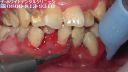

Japonského zubára prekvapil pacient, ktorý si niekoľko desaťročí "pestoval" zubný kameň.

aj dasna ma pekne zapalene